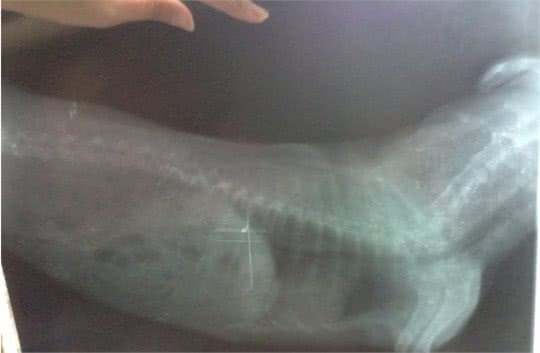

狗狗心脏疾病是最常见的,也是最容易被弄混淆的疾病,因有时候心脏肥大会引起狗狗咳嗽等类似于支气管炎的症状,而持续下去检查结果却是心脏肥大的问题,由于心脏肥大刚好顶到气管,所以才会出现咳嗽的现象。

我们可以把心脏比作成房间,心脏肥大其实就好像是房间的墙壁,肌肉变厚,而整个房间的空间没有增大,反而变小,使整个心脏外观比正常的看起来大,一般一起这种情况的是主动脉瓣膜狭窄、高血液以及遗传性心肌肥厚症。